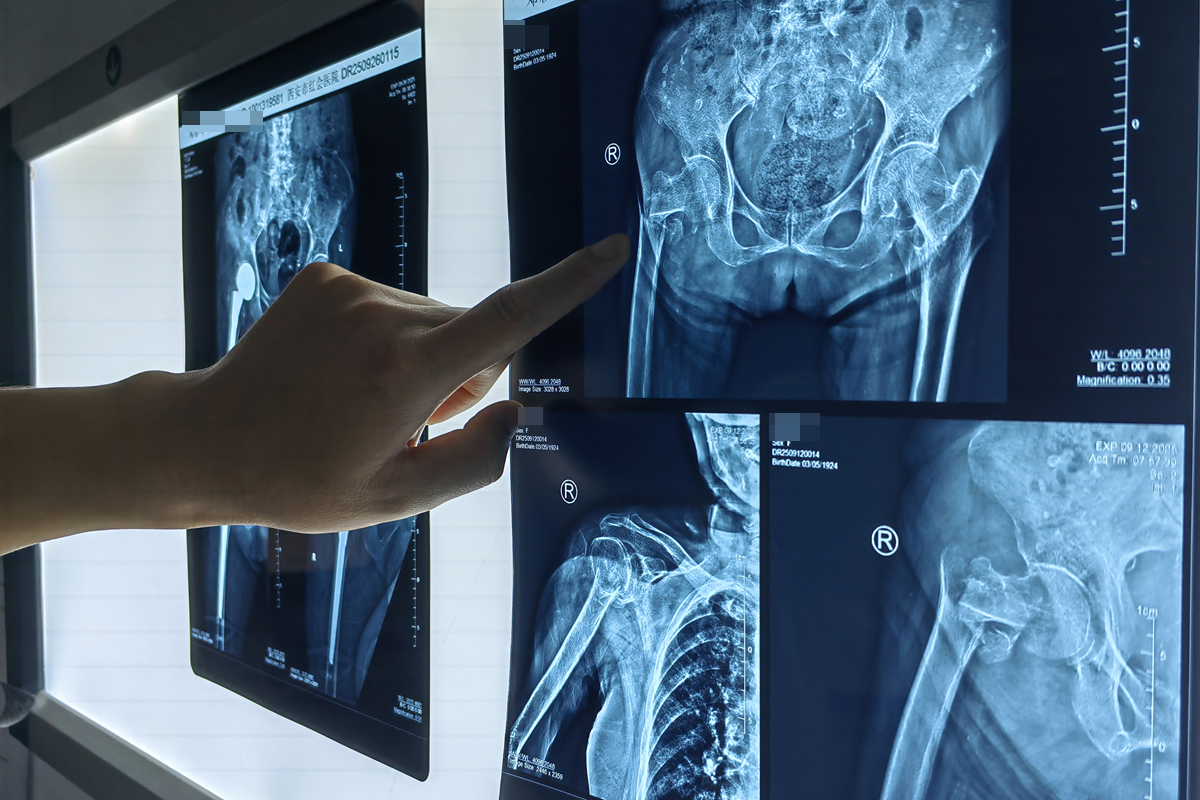

华商网讯(记者 袁毛毛) 近日,一位101岁高龄的股骨粗隆间骨折患者在西安市红会医院关节病院综合病区、心内科、麻醉科等多学科团队(MDT) 的精密协作下,成功接受了直接前方入路(DAA)微创半髋关节置换术。

术前,心内科团队通过心脏超声、冠脉CTA评估心功能,利用药物对患者的心功能进行了优化调整,将血压、心率等指标控制在手术最佳窗口期为手术规划安全航道;术中,麻醉科团队采用椎管内麻醉+轻度镇静方案,既确保手术无痛,又减少了对患者心肺功能和大脑意识的抑制,实时监测数据波动,动态调整用药维持生命体征平稳。骨科团队则采用直接前方入路(DAA)微创技术,经神经肌肉间隙入路,实现7cm小切口、30分钟短时、80ml低出血;术后患者无体位限制,次日即辅助下站立行走,预计将于近日完成康复评估后顺利出院,创高龄患者快速康复范例。